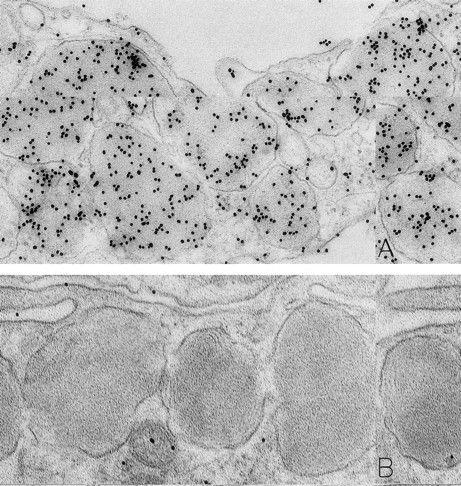

Mast cells in skin biopsies obtained 1 hour 40 minutes (A) or 2 hours (B) after the SC injection of 25 or 5 μg/kg rhSCF, respectively, in patients no. 3 (A) and no. 1 (B), who had received daily SC injections of rhSCF for 13 days. Reactivity for histamine is indicated by DAO-gold labeling in the cytoplasmic granules of a mast cell that exhibits no morphologic evidence of secretory activity (A); DAO-gold label is absent when the grid containing a section of the specimen was digested with DAO before staining with DAO-gold (B). Original magnifications: (A) ×67,500; and (B) ×75,000.